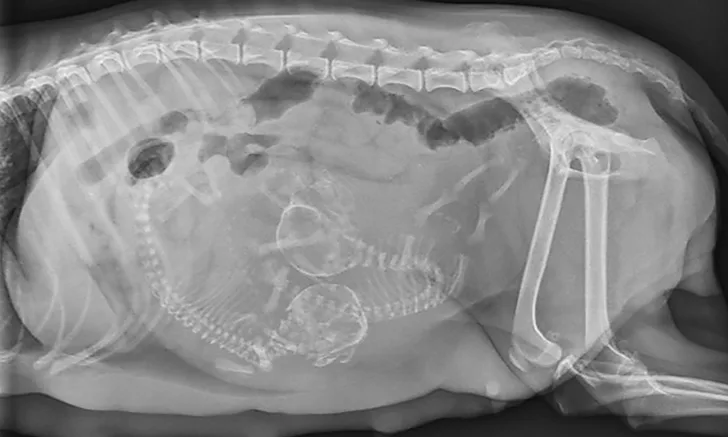

If the bitch is examined after day 44 of gestation, when fetal skeletons mineralize, radiographs should be obtained to determine litter size, fetal positioning, and signs of fetal death.2,8 (See Figure 1 & Figure 2.) Ultrasonography is the ideal imaging modality for determining fetal stress and viability.2